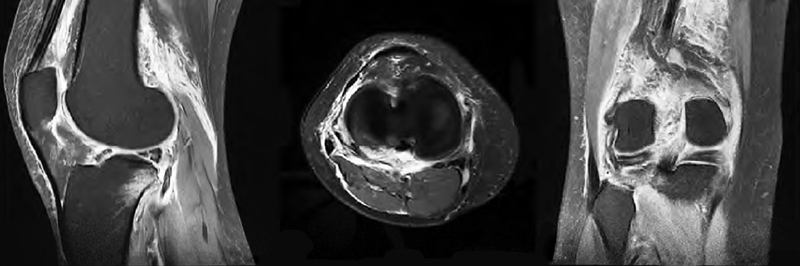

术后第1天复查下肢血管彩超及实验室检查凝血功能,发现腘动脉血栓形成及凝血功能异常(图4~5),患者未诉 不适。体检发现足背动脉搏动较对侧弱,皮温略低,末梢血氧饱和度90%。请显微外科及心血管内科会诊后,心血管内科建议切开取栓,将病情告知患者及家属后行急诊取栓术。术中可见腘动脉分叉近端约2cm大小的半月板缝合袢将腘动脉捆扎,但仍有血流通过(图6),切开血管,取出血栓,取出半月板缝合袢,松开止血带,见血流好,在显微镜下修复腘动脉,再次松开止血带,见动脉搏动良好,无漏血,足背动脉搏动好,末梢血氧饱和度99%,手术完毕。患者术后第1天开始主动活动,双侧皮温一致,未诉患肢疼痛,复查右下肢动静脉彩超示右侧动静脉血流通畅(图7),术后24个月随访患者右下肢活动功能良好,双下肢无明显肿胀,双侧皮温一致,小腿腿围基本一致,患者McMurray征阴性,前抽屉试验阴性,膝关节稳定性良好,活动度良好。

图4 术后 第1天彩超可见一条索状与心率一致的搏动性阴影(红色虚线区 域),提示右侧腘动脉血流减缓